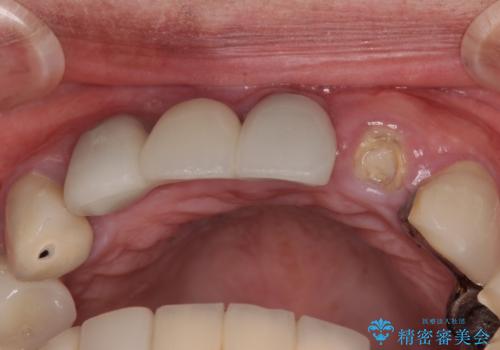

歯根周辺の骨や歯肉の状態は良く、抜歯して速やかにインプラントを埋入し、即日で仮歯を装着するプランにて治療を行うこととしました。

初回カウンセリング時にはセラミッククラウンが装着されていましたが、インプラント治療でのご来院時には前歯は外れて紛失をしてしまったとのことでした。

事前に仮歯の型取りをして用意をしていたため、インプラント埋入後に速やかに仮歯を装着しました。